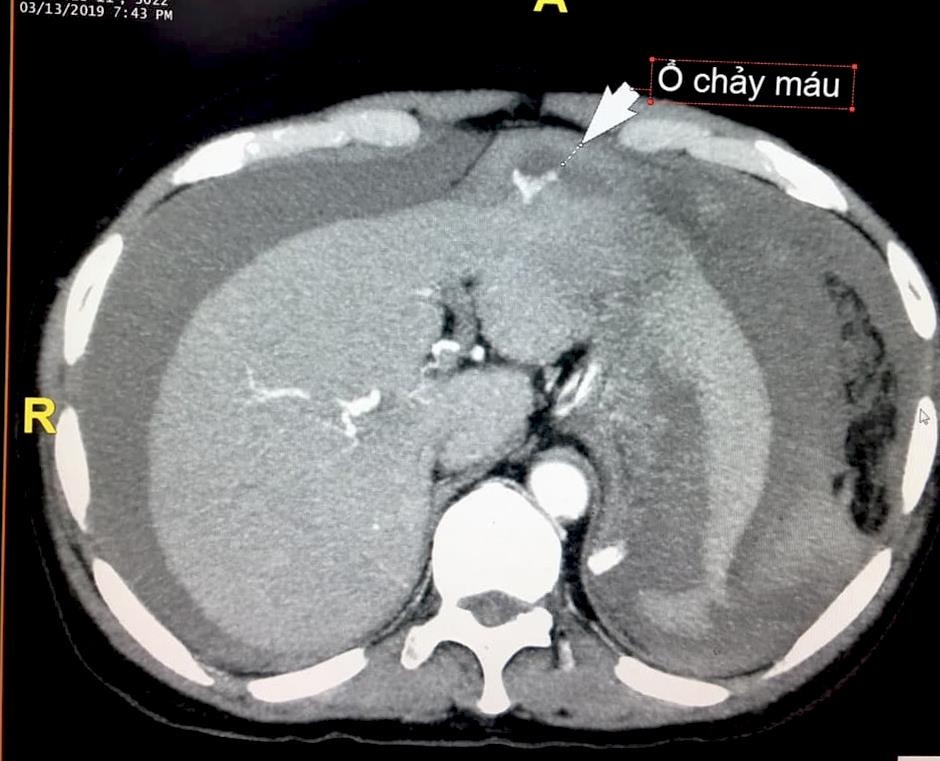

Kết quả chụp phim cho thấy bệnh nhân bị chảy máu, đọng nhiều trong ổ bụng. Tiến hành xét nghiệm, bác sĩ nhận thấy bệnh nhân mắc u gan trên nền xơ gan. Khối u bị vỡ khiến máu chảy vào ổ bụng.

| Khối u trong gan bệnh nhân bị vỡ khiến máu chảy tràn ra ổ bụng. Ảnh: Bác sĩ cung cấp. |